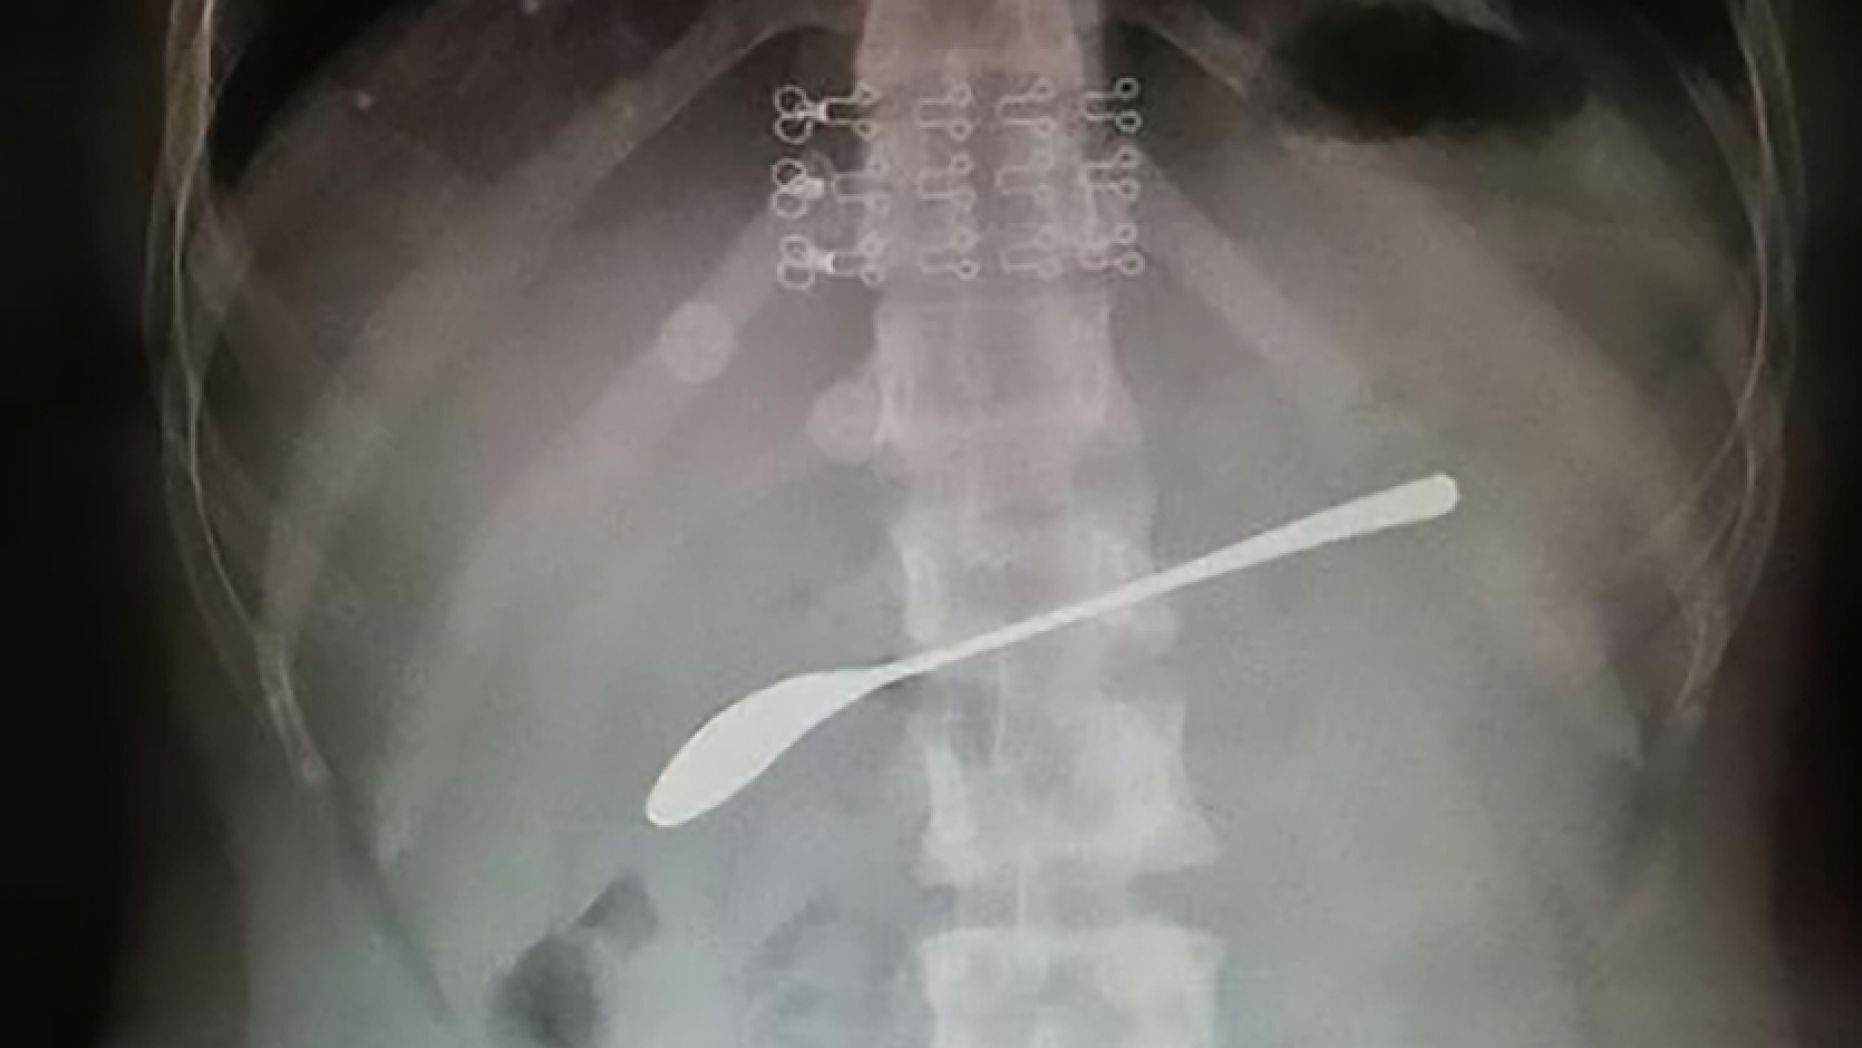

An X-ray revealed the 6-inch spoon in her abdomen to be the cause, AsiaWire reported. Rather than open her stomach, Dr. Fan Guangxue decided on a gastroscopy procedure, which involves inserting a thin tube down a patient’s throat.

This X-ray shows a 6-inch steel spoon resting inside the stomach of a young woman who drunkenly swallowed it the night before and forgot about it until her stomach began hurting the next day. (AsiaWire)